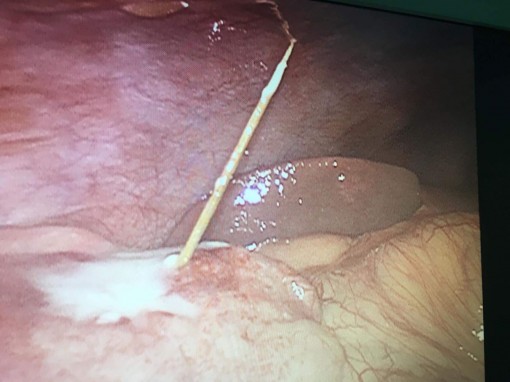

Thủng ruột do tăm xỉa răng

(CTO)- Các bác sĩ ở Bệnh viện Đa khoa Trung ương Cần Thơ vừa phẫu thuật nội soi thành công ca thủng ruột non hy hữu do tăm xỉa răng.